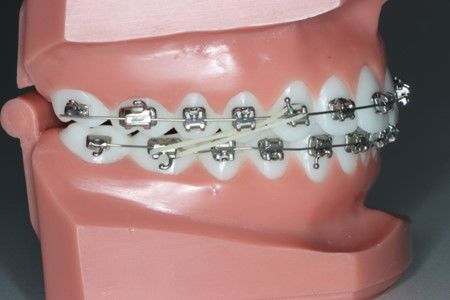

Bruges ofte sammen med fastsiddende apparatur til at gøre overbiddet mindre, kan også bruges til enkelttandskorrektioner, som f.eks. krydsbid.

Kan have forskellige størrelser og kræfter.